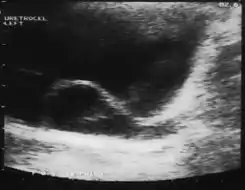

Imagen de ureterocele:

El diagnóstico puede establecerse por ecografía de todo el tracto urinario (técnica de diagnóstico por imágenes que utiliza ondas de sonido de alta frecuencia, que tras atravesar tejidos de diferente densidad, son computabilizadas, dando una imagen de los vasos sanguíneos, tejidos, órganos internos, colecciones de líquido, masas, etc.). En ocasiones debe realizarse una pielografía endovenosa (PEV) que es una técnica diagnóstica radiológica en la que se administra un contraste endovenoso, que durante su excreción por la vía urinaria permite visualizar mediante radiografías seriadas, la velocidad y trayectoria del flujo urinario. También permite detectar alteraciones morfológicas congénitas (duplicidad pielocalicilar) o patológicas (hidronefrosis, obstrucciones intrínsecas y extrínsecas, etc.). UROGRAMA ESCRETOR,CISTOURETEROGRAFIA MICCIONAL EN PACIENTES ADULTOS